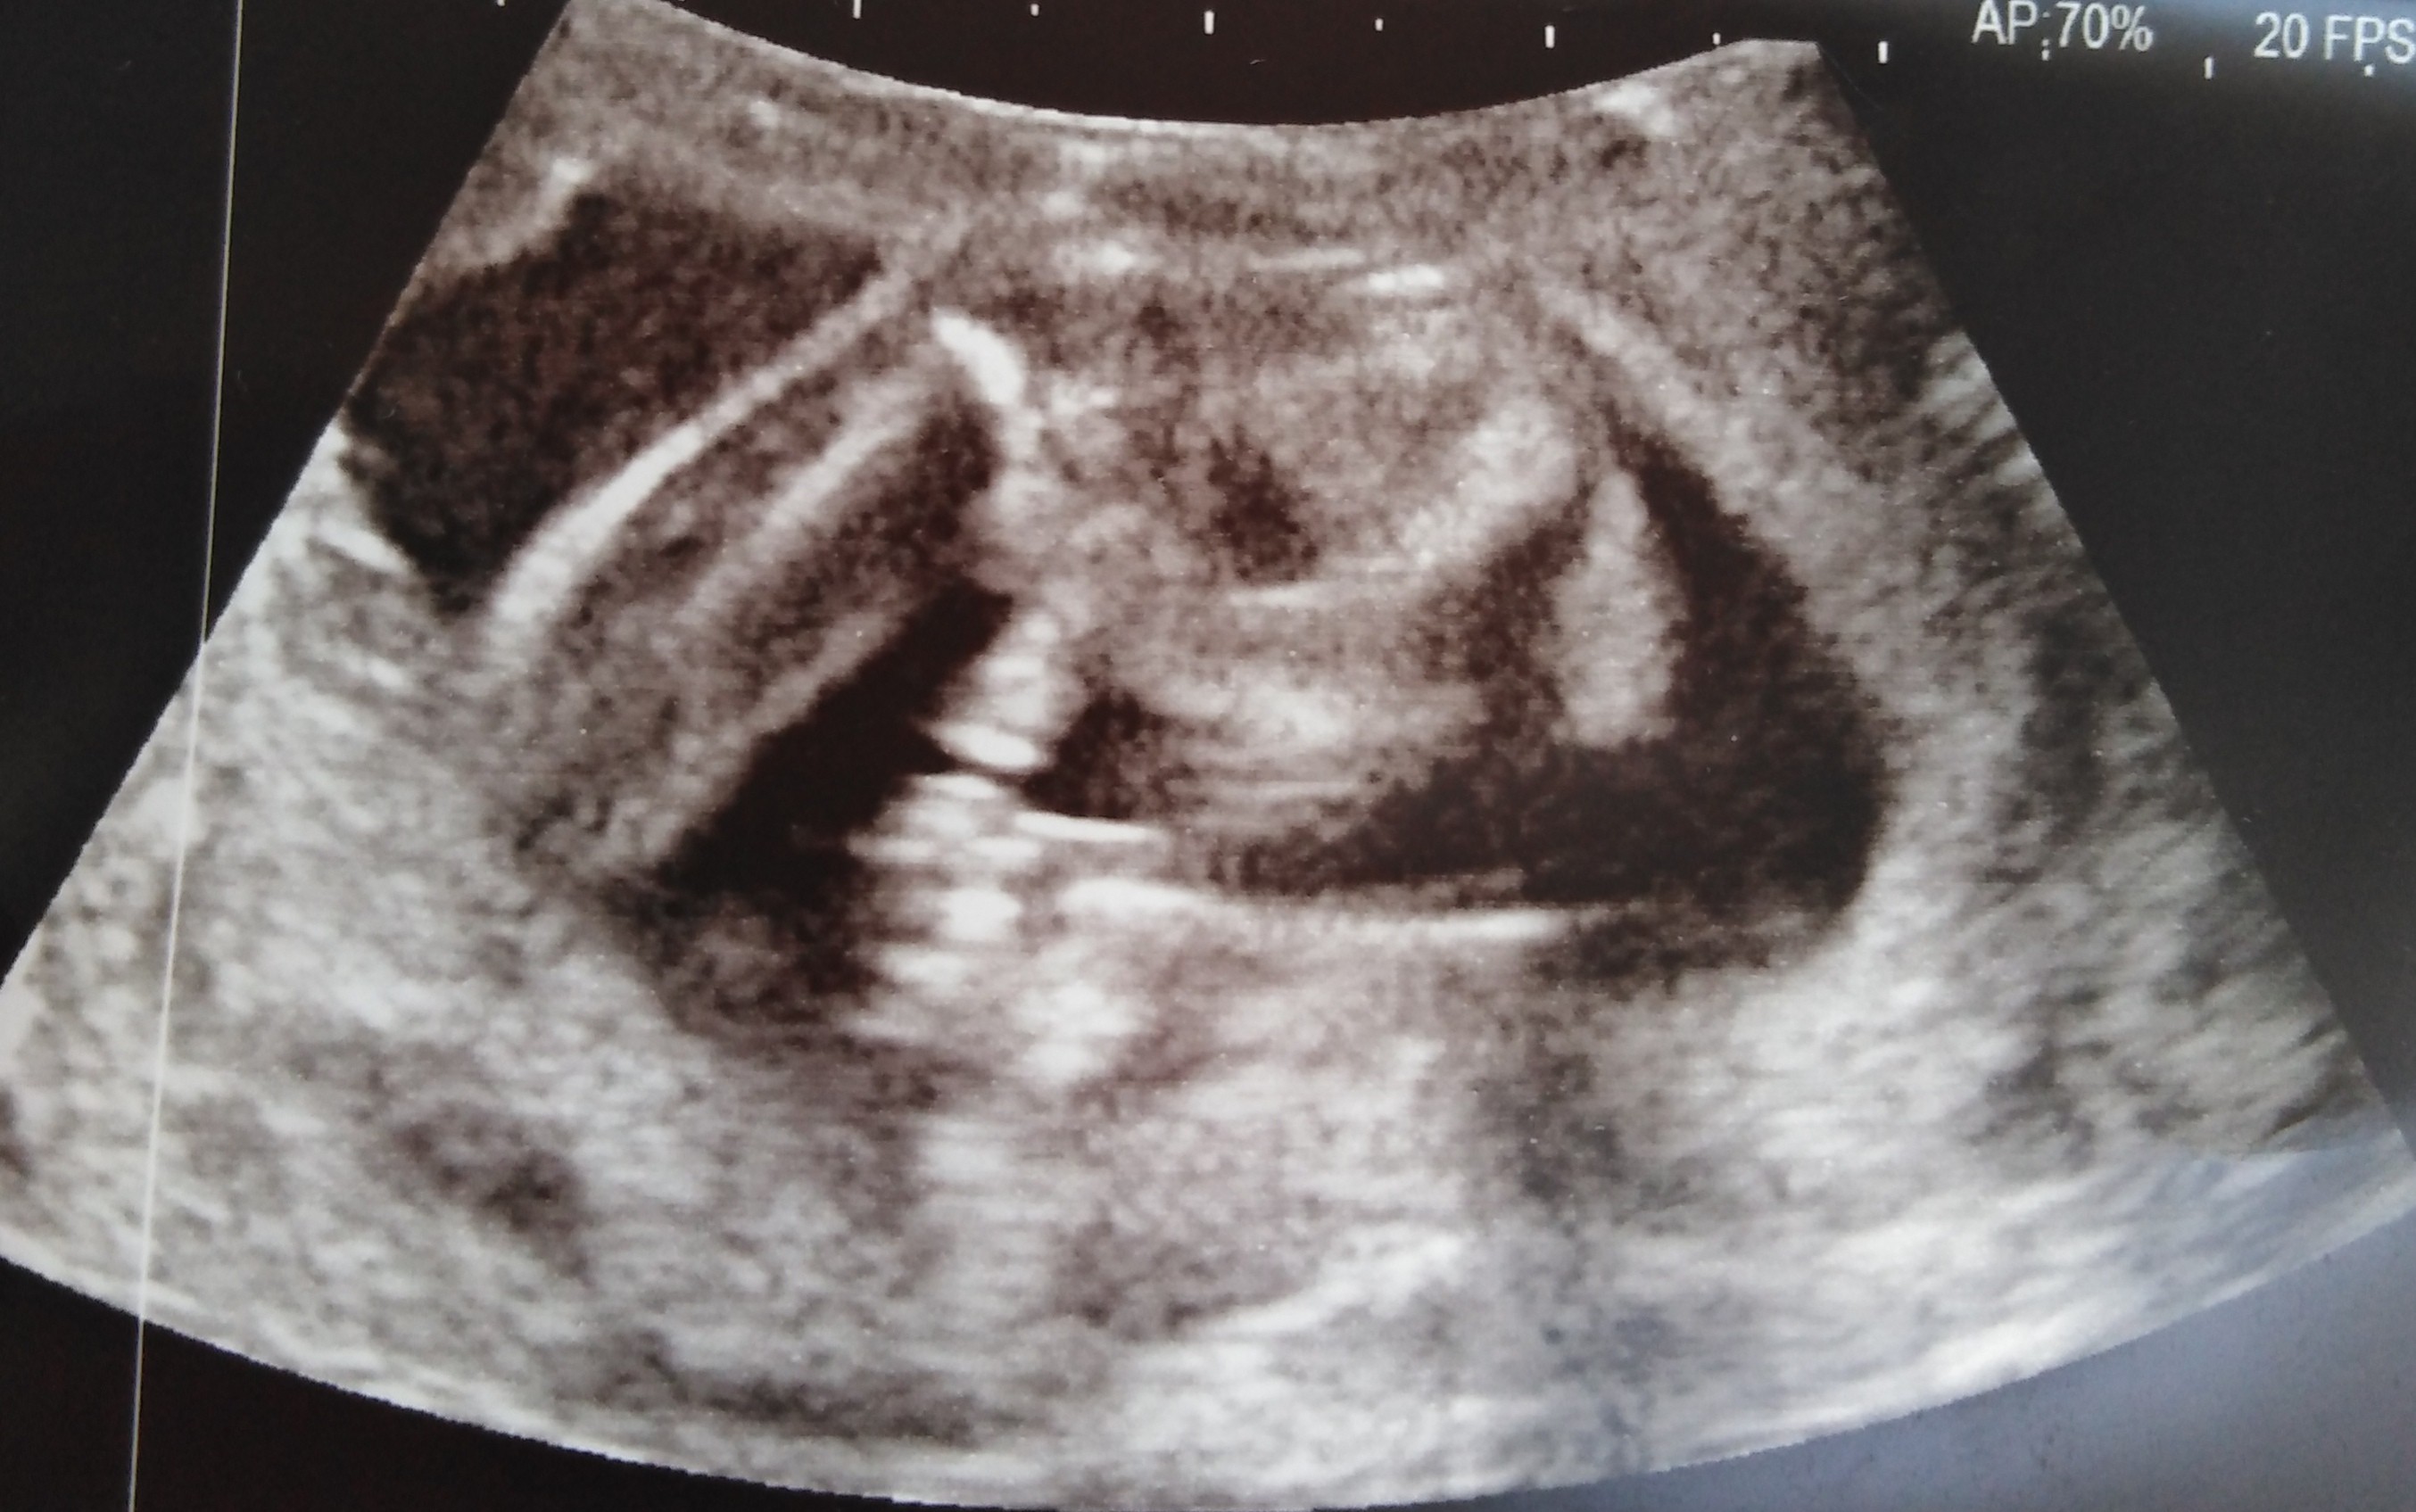

Cześć dziewczyny proszę was o ocenę zdjęcia usg... Miesiąc temu zapowiedzieli mi syna a 4 grudnia na połówkowym ze córka... Trochę mam mętlik w głowie 😞

I czy ten „cypelek”na nubie o czymś świadczy czy maja go zarówno chłopcy jak i dziewczynki

Zżera mnie ciekawość, choć gdzieś w środku czuje ze druga córa się szykuje zamiast synka...

• E622F8B3-4E12-4F76-A34E-879251B1E76F.jpeg

E622F8B3-4E12-4F76-A34E-879251B1E76F.jpeg

295,3 KB · Wyświetleń: 416